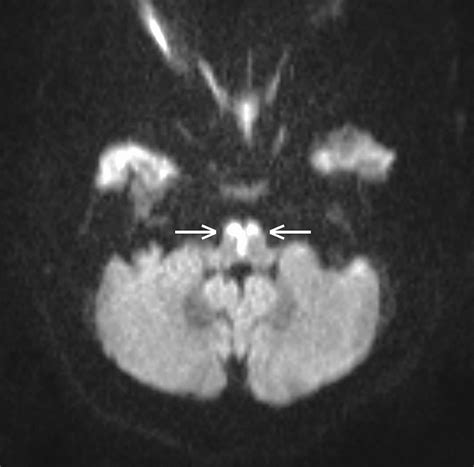

To confirm a Lateral Medullary Stroke, physicians rely on advanced imaging techniques. While a CT scan is often the first line of defense to rule out hemorrhage, it is frequently insensitive to small strokes in the brainstem. Therefore, a diffusion-weighted MRI (DWI-MRI) is the gold standard for visualization.

MRI (Magnetic Resonance Imaging) Best for identifying infarctions in the brainstem tissue.